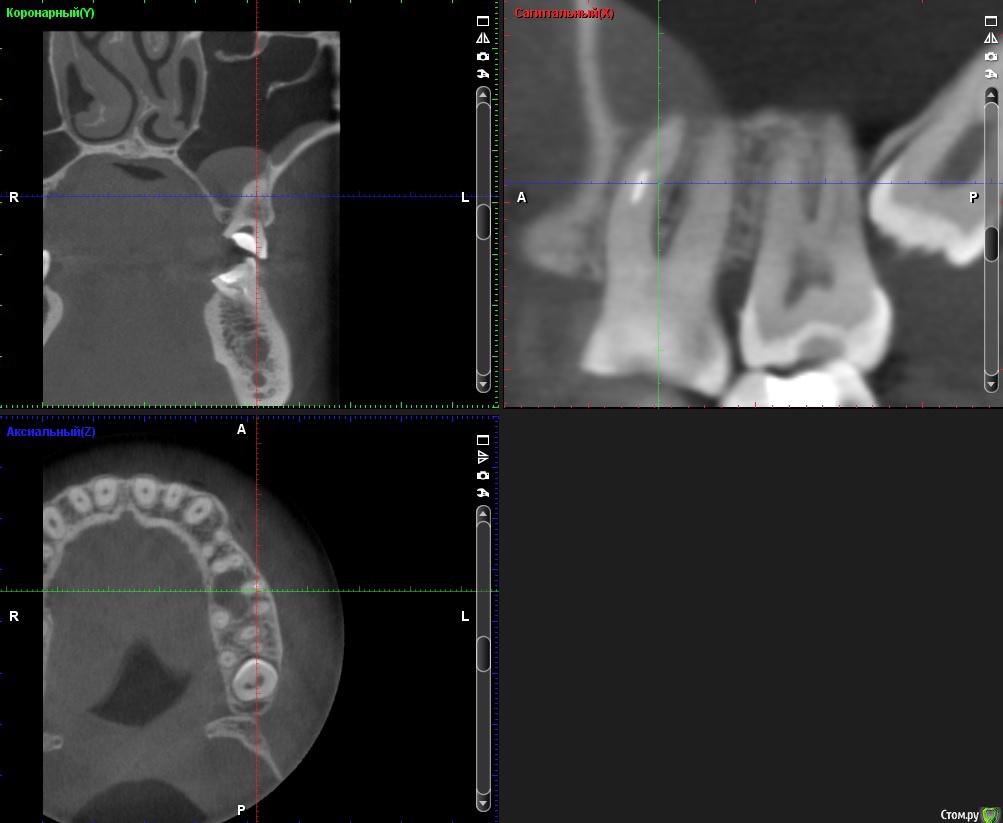

ClayMixer Опубликовано 18 ноября, 2016 Поделиться Опубликовано 18 ноября, 2016 (изменено) Здравствуйте! Вопросы по двум зубам (36 и 26): 1. Киста (36-ой зуб).Консультировалась у нескольких врачей. Мнения разные. От "можно поставить вкладку и коронку на n-ное количество времени до удаления; эту кисту не вылечить", до: "только удаление, желательно быстрее". 1) Можно ли вылечить этот зуб? И каков процент успеха?2) Есть ли смысл лечить зуб и ставить вкладку и коронку или лучше удалить и делать имплант? После того, как 36 зуб подготовили под вкладку - бывали неприятные непонятные ощущения (похожие на импульсы), не острые (длительностью 3 нед.) Вроде после этого времени стали утихать понемногу. 2. Инородное тело (обломок инструмента) в 26-м зубе.Врачи пытались извлечь его (без микроскопа) - безуспешно. Канал, в котором "застрял" инструмент не до конца "пройден".Критично ли это? Какова вероятность воспаления? (теперь патологический страх появления кисты ) Теоретически можно ставить вкладку и коронку? Ходила таким трансформером больше 5-ти лет, не беспокоил вообще. После попыток врачей достать инструмент также бывали неприятные непонятные ощущения (похожие на импульсы), не острые (длительностью 3 нед.) Вроде после этого времени стали утихать. При простукивании коронки обеих зубов болевых ощущений вроде не наблюдалось. Результаты КТ https://cloud.mail.ru/public/Fhy4/ESmeyU9hp Изменено 18 ноября, 2016 пользователем ClayMixer Ссылка на комментарий

ClayMixer Опубликовано 18 ноября, 2016 Автор Поделиться Опубликовано 18 ноября, 2016 26-ой зуб Ссылка на комментарий